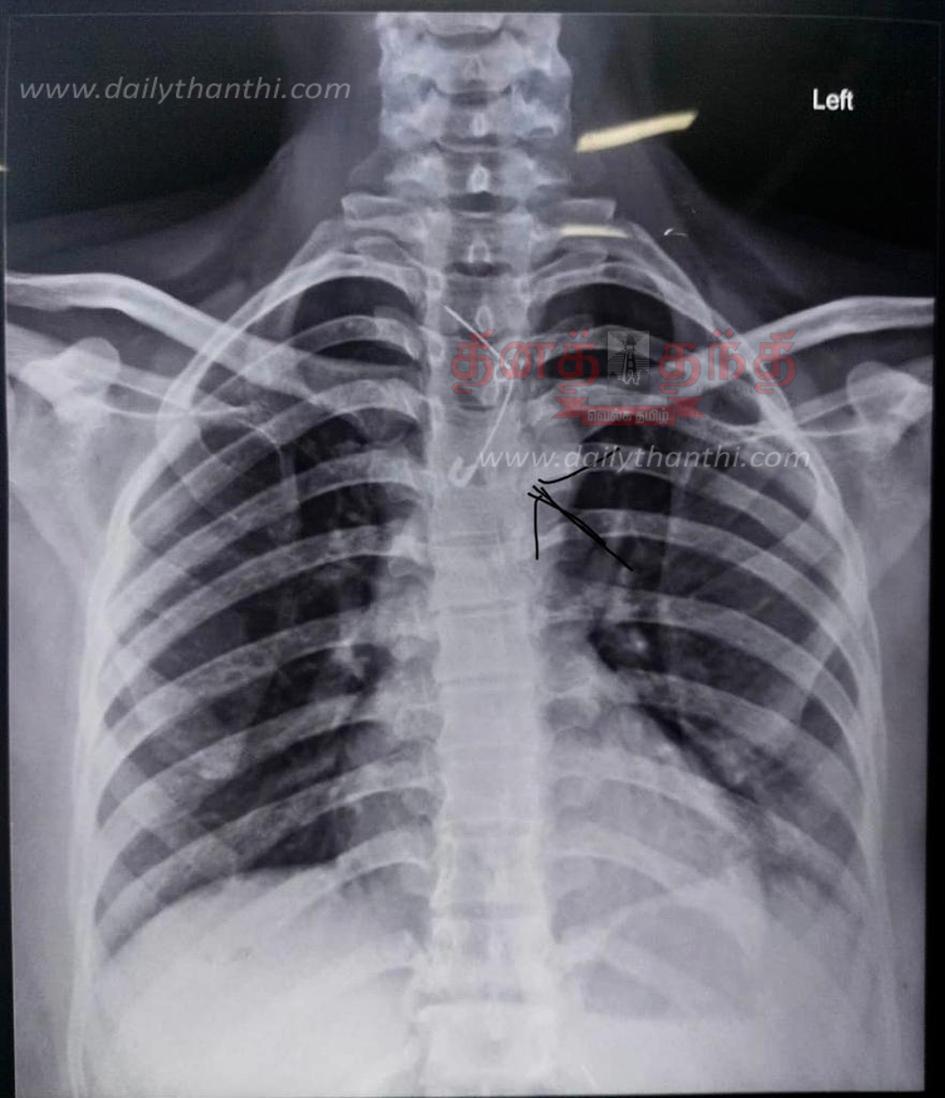

இதையடுத்து டாக்டர்கள் கலாவுக்கு உடனடியாக சிகிச்சையை தொடங்கினர். கலாவுக்கு தொண்டை பகுதியில் எக்ஸ்ரே உள்ளிட்ட பரிசோதனை செய்து பார்த்தபோது, நெஞ்சு பகுதியின் உணவு குழாயின் மேல் பகுதியில் அந்த 'ஊக்கு' சிக்கியிருப்பது கண்டறியப்பட்டது. பின்னர் டாக்டர்கள் உடனடியாக எண்டோஸ்கோபி சிகிச்சைக்காக மயக்க மருந்து கொடுத்து ஊக்கை அகற்ற ஏற்பாடு செய்தனர்.

பிறகு அறுவை சிகிச்சை இல்லாமலேயே எண்டோஸ்கோபி கருவியை உணவுக்குழாயில் செலுத்தி அங்கு சிக்கி இருந்த ஊக்கை நோயாளிக்கு எந்த பாதிப்பும் இல்லாமல் டாக்டர்கள் அகற்றினர். சிறிது நேரத்தில் மயக்கம் தெளிந்த கலா, தொண்டையில் சிக்கி இருந்த 'ஊக்கு' அகற்றப்பட்டதை அறிந்து நிம்மதி பெருமூச்சு விட்டார்.